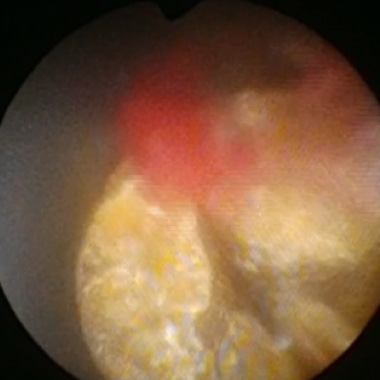

HoLEP

ホルミウムレーザーによる腺腫の核出(内腺のくり抜き)

腺腫の核出後